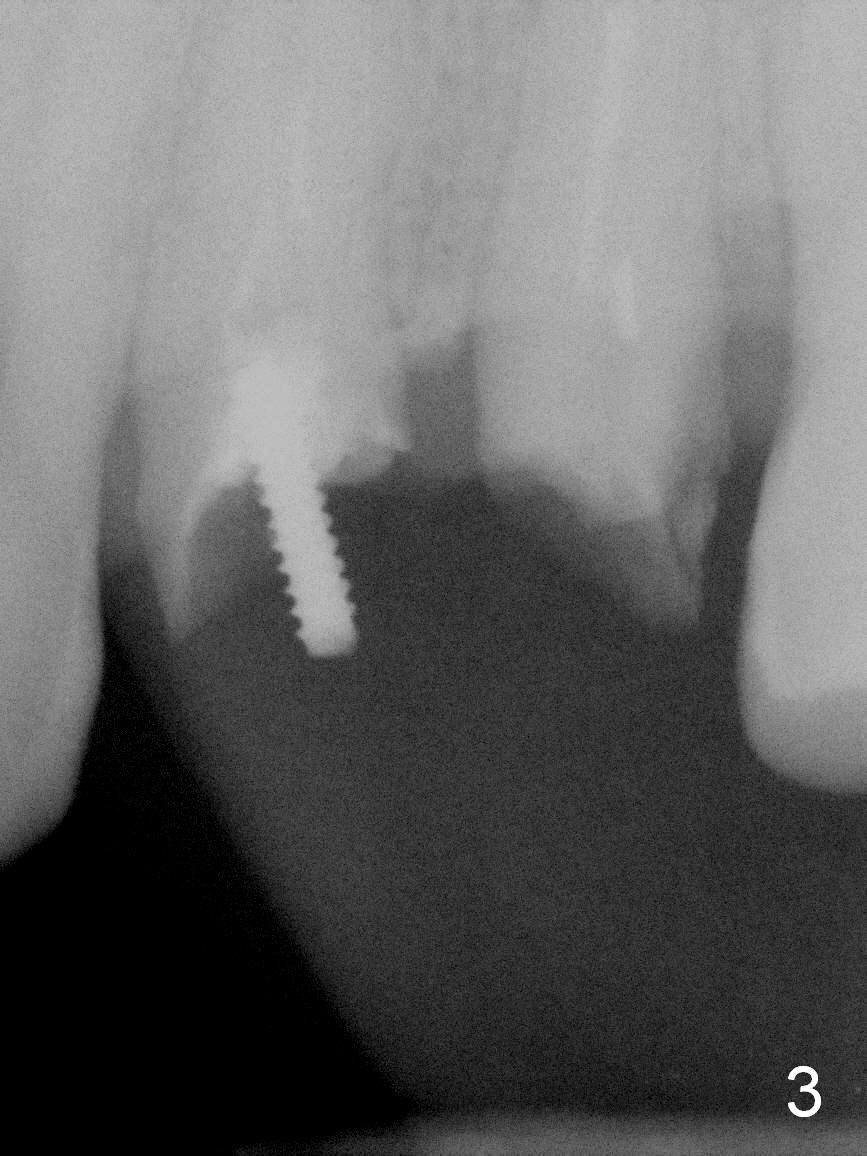

A 45-year-old man presented to our office 8 years ago (Fig.1,2) and got work done somewhere else. He returned yesterday with chief complaint "I might swallow my crowns". Exam shows residual roots at #12,13 (Fig.3,4). The patient has strong jaw bone, suggesting that the bone density is high. Either bone- (Fig.5) or tissue- (Fig.6) level implants will be placed. By time sequence, this case will be assigned to the control group of the antibiotic study. Preop PA does not catch the apices (Fig.3). Take a new one with sensor 1 prior to surgery or panoramus.